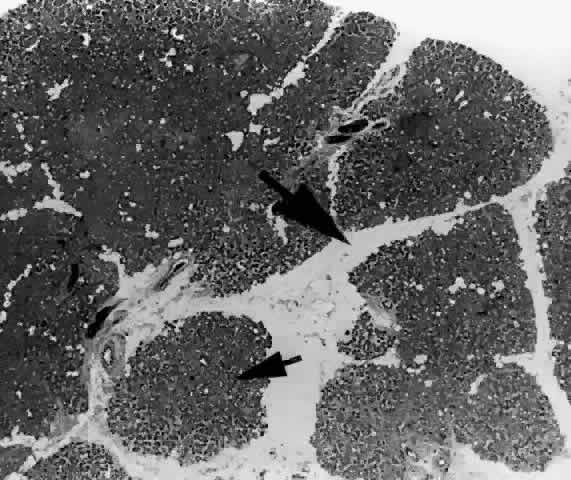

Each lobe of the lacrimal gland is separated into numerous lobules by interlobular fibrovascular connective tissue (Fig. 11). Each lobule, as seen by light microscopy, is composed of two units (Fig. 12): (1) the acinar unit (or secretory unit); and (2) the ductal system. The acinar units are further separated by intralobular fibrovascular connective tissue.

Fig. 11. Lacrimal gland architecture. Each lobe of the lacrimal gland is separated into numerous lobules by interlobular fibrovascular connective tissue. (H & E, original magnification × 5; Courtesy of Ralph Eagle, MD, Philadelphia, PA)

Fig. 14. Tubuloracemose architecture of the lacrimal gland. Interlobular fibrovascular connective tissue (large arrow) separates the lobules of acinar tissue (small arrow). (H & E, original magnification × 5; Courtesy of Ralph Eagle, MD, Philadelphia, PA)